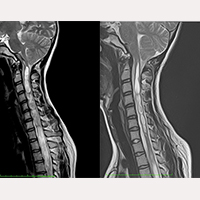

후두하 두개골 절제술 후 SFT

1993년 10월부터 2017년 7월까지 1,000명 이상의 아놀드 키아리 증후군 제1형, 척수공동증, 척추측만증(질병들이 다양하게 조합된 형태로)을 동반한 신경-두개골-척추 증후군 또는 종사 질병에 걸린 환자들이 종사 시스템® 프로토콜에 따른 치료 및 수술을 받았습니다.